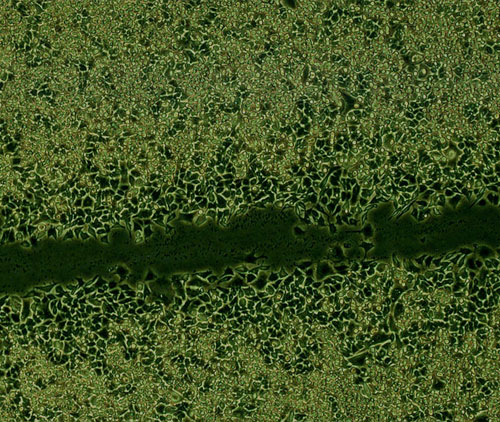

細(xì)胞劃痕+流式